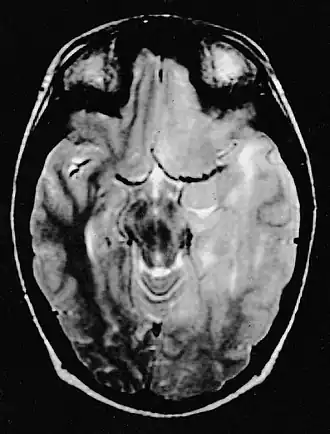

![]() La imagen de RM ponderada en T2 muestra (en el lado derecho) la infiltración difusa del tumor. | ||

En las imágenes de resonancia magnética, el tumor aparece como una lesión difusa, poco circunscrita, infiltrante y sin captación de contraste, con señal hiperintensa en las imágenes ponderadas en T2, y que se expande hacia la materia blanca. Puede ser difícil de distinguir de un astrocitoma anaplásico altamente infiltrante o un glioblastoma.[6]

La característica radiológica más frecuente en la RM es la infiltración en forma de lesión hiperintensa en T2 y FLAIR tanto de la sustancia blanca como de la sustancia gris. Con la administración de contraste el realce es mínimo o ausente.[14][15]